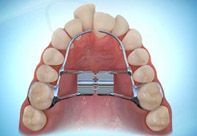

Other types of orthodontic appliances may also be used during the course of treatment. Some of these appliances are removable and can be taken in and out of the mouth, while others will be attached to the teeth until they are no longer needed.

Depending upon the specific needs of the case, these appliances may be used to accomplish a number of things including:

- Widening the jaws to make sufficient space for permanent teeth

- Influencing jaw growth

- The reduction of deep overbites

- Allowing the correction of teeth in crossbite

- Maintaining the space for a permanent tooth when a baby tooth has been prematurely lost

- Minor tooth movement

- Helping to control harmful oral habits